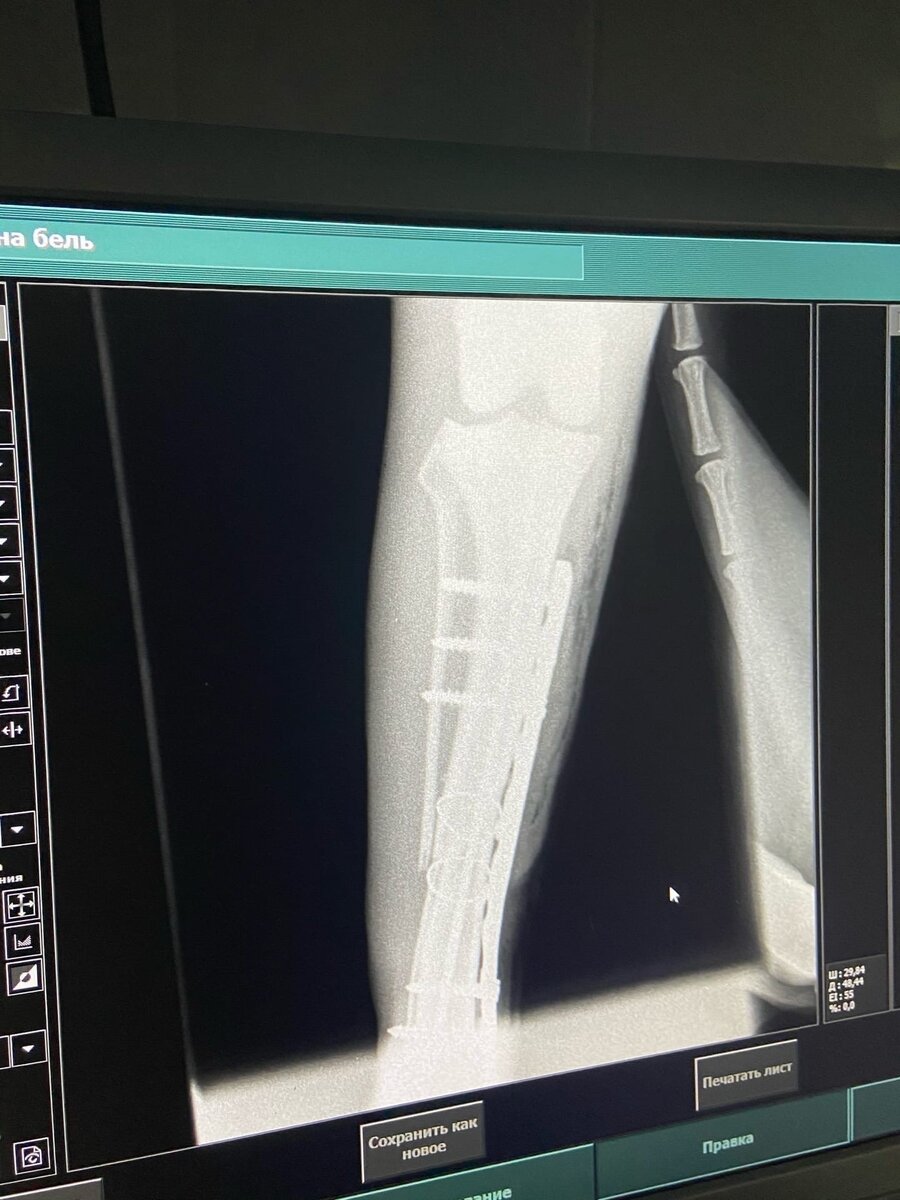

Ладу нашли беспомощно лежащей на дороге, сбили ее или избили, к сожалению, она не может нам рассказать. Много ран, сломанное ухо, открытый перелом, понадобилась операция.

Сейчас она находится на передержке с медуходом. Видно, что ей доставалось от "добрых людей" она вся сжимается, когда к ней подходишь, но это не помешало ей остаться доброй, она терпит все уколы и обработки и ни разу даже не оскалилась, только прячет глаза. Друзья, опять приходится просить о помощи, но без ваших пожертвований нам не справиться. Сумма не маленькая, но вместе мы справимся.